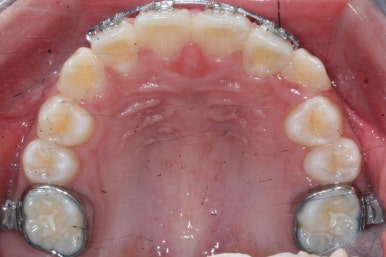

장치를 부착한 후에 순차적으로 변화가 나타나는 모습입니다.

총 4장의 사진 동안 경과한 시간은 불과 6개월 입니다. 헤드기어를 통해 사전에 작업을 해뒀기 때문에 이후 연산동덧니교정 과정은 편해진 것이죠.

윗니만 6개월이 지난 모습입니다.

치열이 매우 가지런해졌죠. 이 후에는 특이사항 없이 종료가 되었습니다.